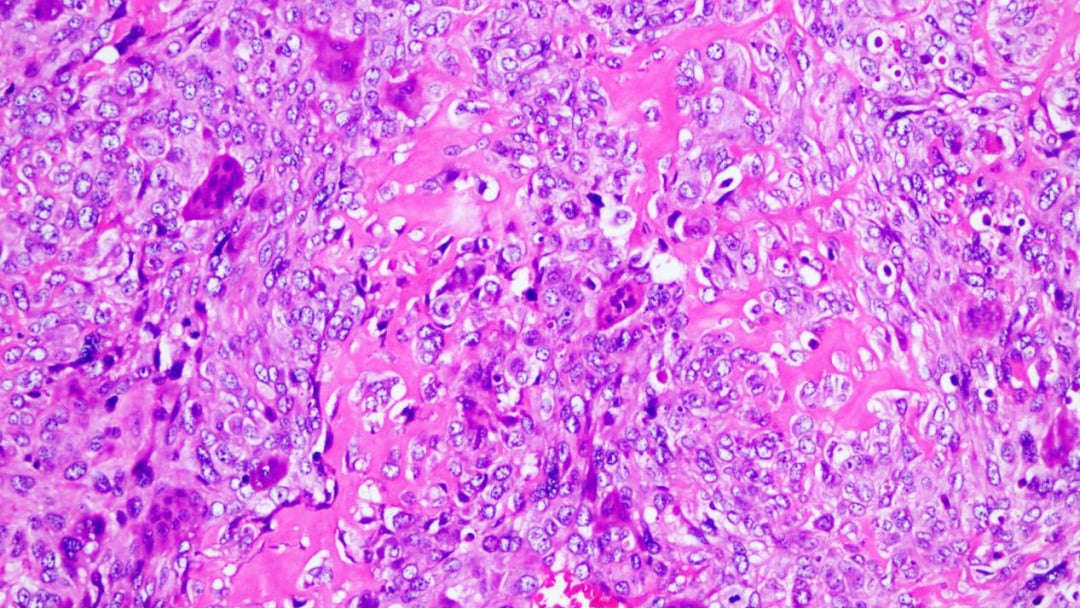

- 高度恶性特征:肿瘤细胞表现出高度的异型性,细胞大小不一,核深染,形态怪异。病理性的核分裂象(癌细胞分裂的标志)随处可见,这预示着肿瘤具有很强的增殖和侵袭能力。

- 关键诊断依据:最关键的发现是肿瘤组织中产生了花边状的骨样组织和软骨样基质,这是诊断骨肉瘤的决定性证据。此外,组织中还散在分布着破骨样多核巨细胞。

高倍镜下,可见骨样组织及破骨样多核巨细胞

高倍镜下,肿瘤细胞高度异型性,可见多个病理性核分裂象